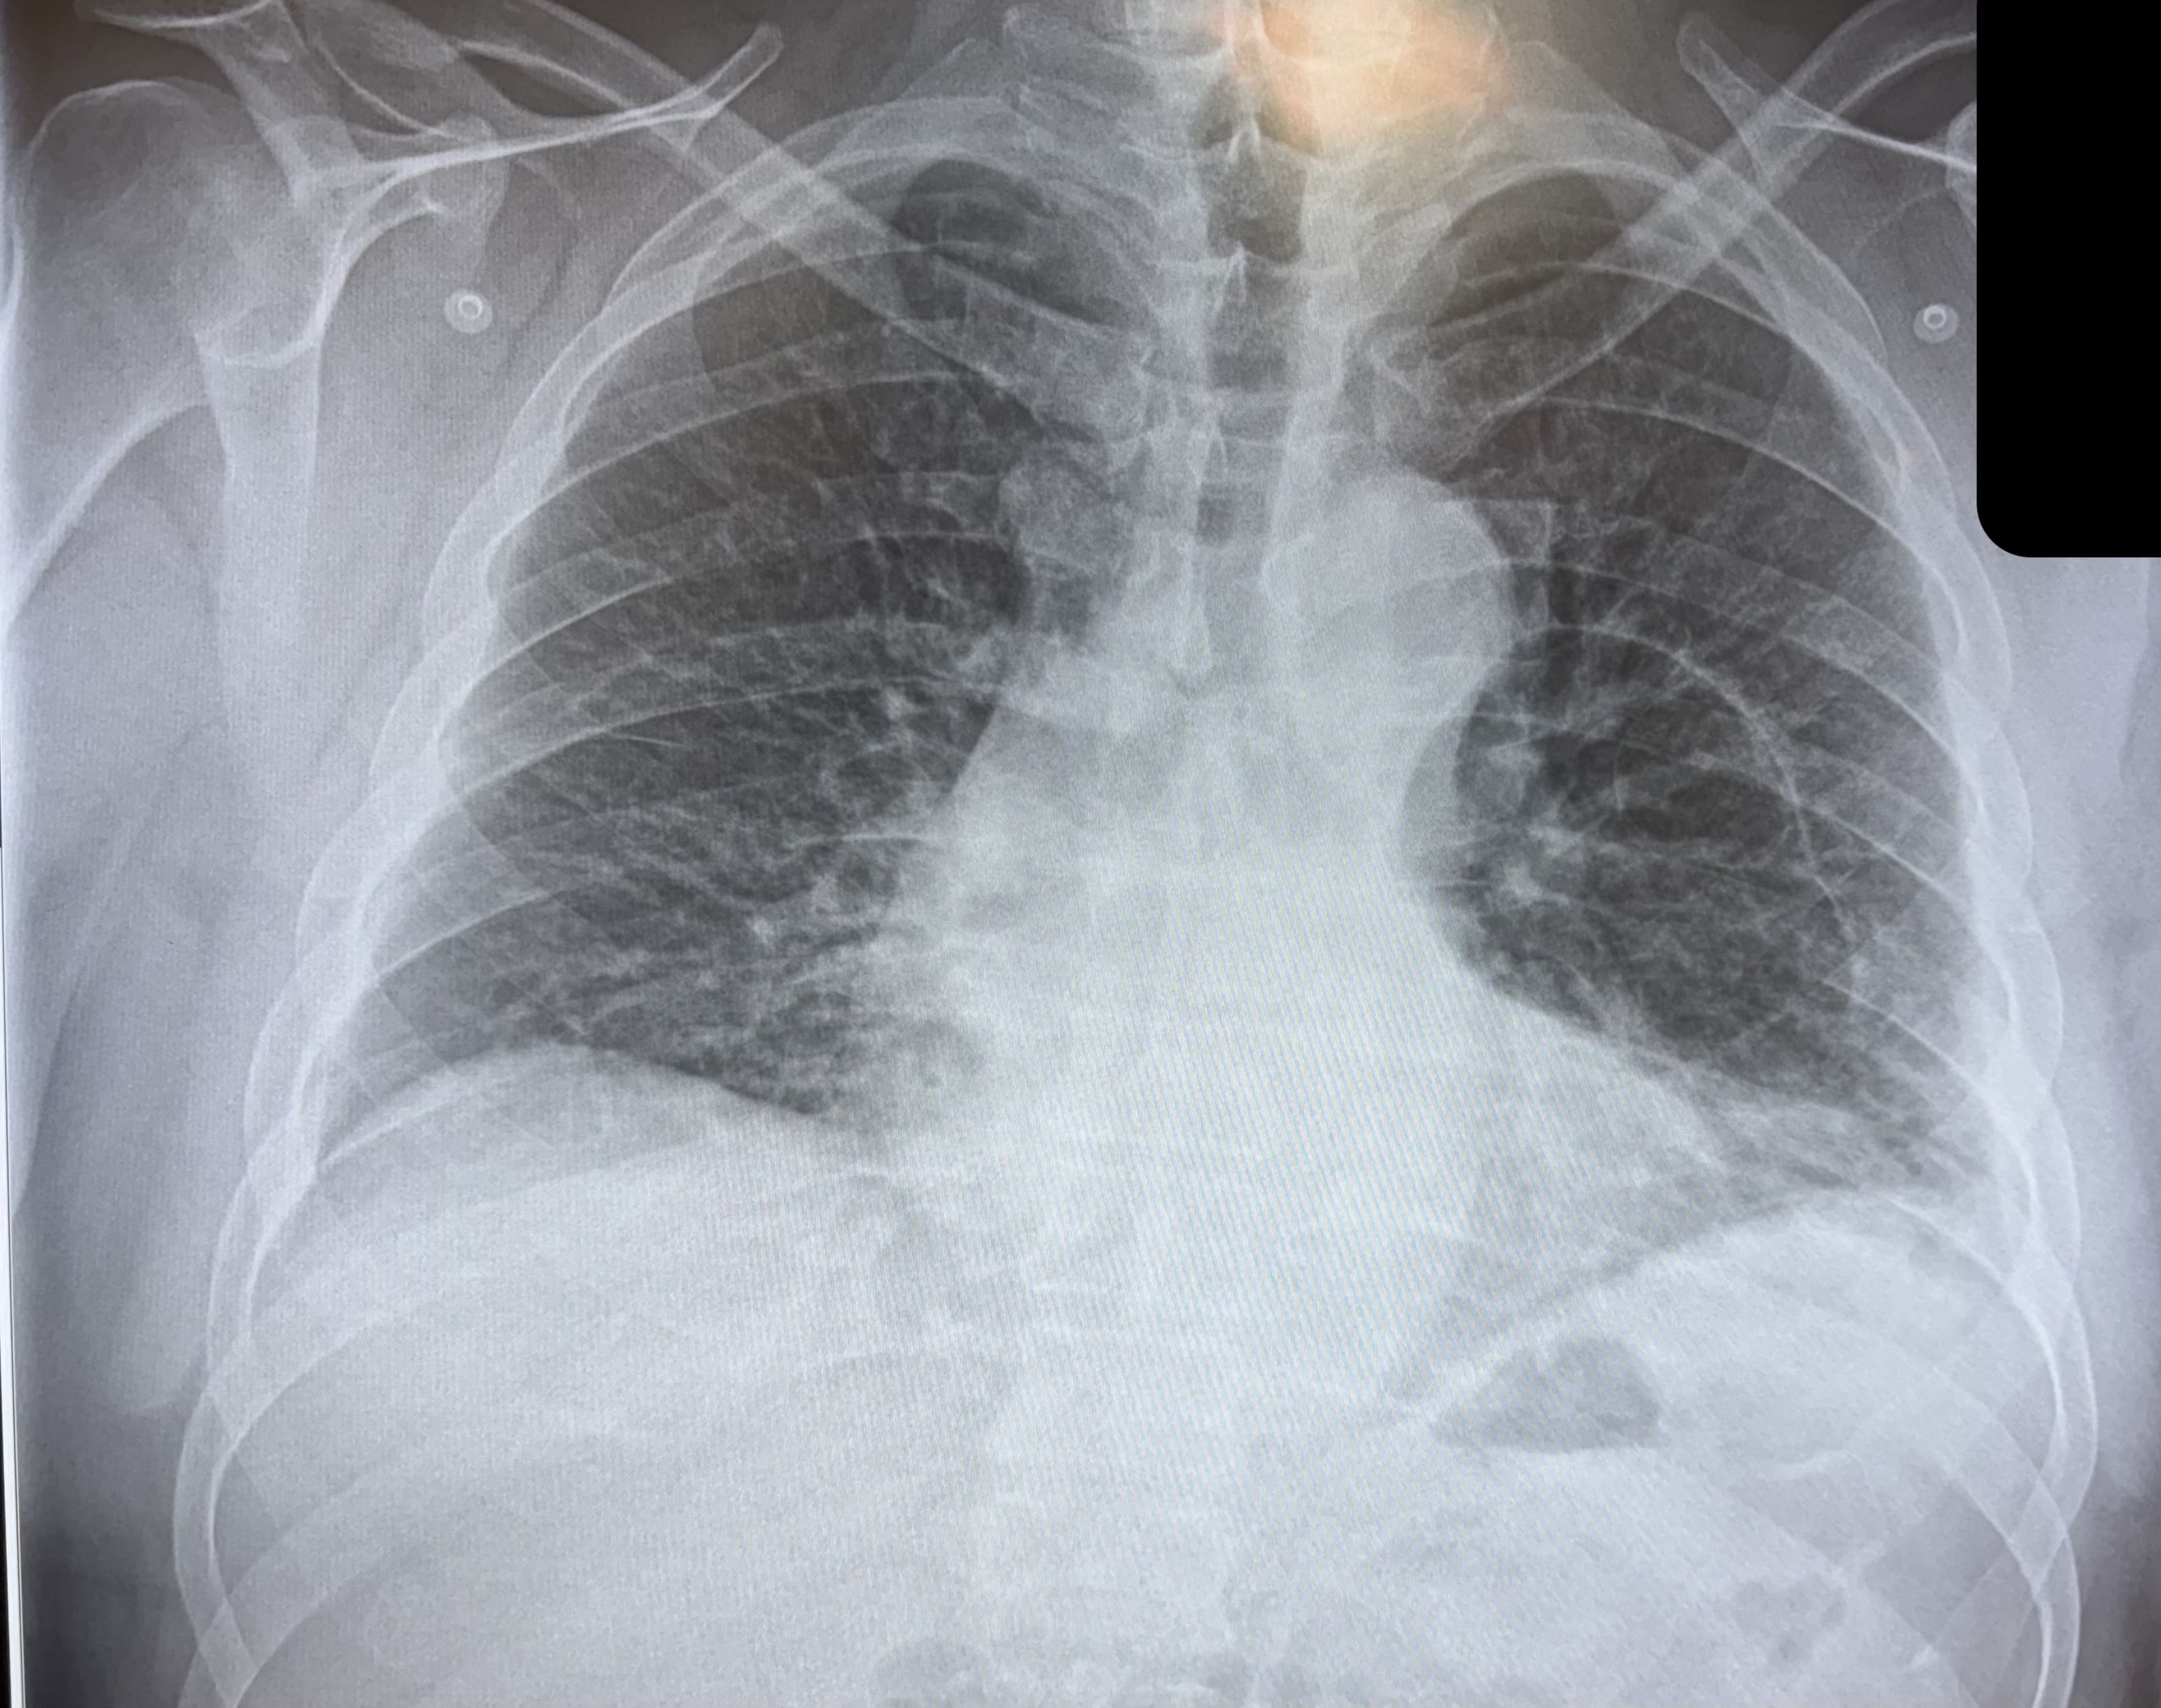

Así pues, se confirma la existencia de una neumonía basal izquierda. Decido, pues, realizar analítica sanguínea con hemograma y bioquímica, que confirma parámetros de características infecciosas con leucocitosis de 15.000 m con 9.300 segmentados y PCR 9,38 mg/dL. Resto de parámetros, incluyendo troponina, en rango de normalidad. ECG normal y radiografía de tórax con bulla ya conocida parahiliar izquierda, resto normal.

A veces, los hallazgos clínicos de un paciente (sus signos, síntomas...) no coinciden con los resultados de las pruebas de imagen. La discordancia clínico-radiológica, pues, existe. Este caso es un buen ejemplo de ello: el paciente tenía una neumonía, pero la imagen radiológica no fue capaz de visualizarla. Esto, a menudo, implica al profesional a reconsiderar y reevaluar el diagnóstico inicial, buscar nuevas explicaciones para los síntomas presentes...